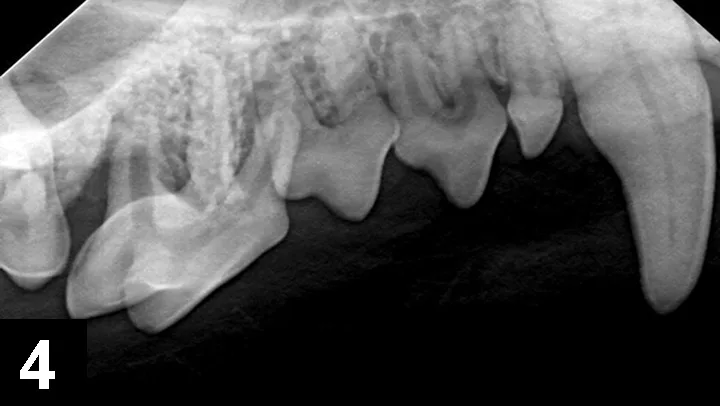

A parulis is an opening of an intraoral sinus tract in the oral mucosa; hidden periodontal disease is often indicated if the parulis is within the gingiva (Figures 3 and 4). Periodontal disease is caused by a subgingival biofilm (an adherent bacterial community living in an exopolysaccharide matrix that protects the bacteria and allows cooperation of the microorganisms) that results in loss of attachment of the periodontium (ie, gingiva, alveolar bone, periodontal ligament, cementum), regardless of the amount of plaque or calculus on the supragingival crown. Periodontal disease is predominately a subgingival disease, so general anesthesia and intraoral radiographs are required. Extraction is often necessary for periodontal disease associated with a parulis. If the parulis is within the oral mucosa, it is likely caused by endodontic disease, and root canal treatment may be an option. A parulis at the mucogingival junction might be caused by either periodontal or endodontic disease.

Parulides at the mucogingival junction of the right maxillary fourth premolar (tooth 108). Although the crown does not appear clinically fractured or to have significant plaque and calculus, the presence of the parulides indicates infection resulting in sinus draining tracts exiting in these regions. Intraoral radiographs are indicated.

Combined vertical and horizontal bone loss of the distal and buccal roots of tooth 108 from the patient in Figure 3, resulting in almost complete bone loss. The tooth has a wide pulp canal compared with other teeth, indicating the pulp in this tooth died a long time ago (combined periodontal–endodontic disease). Surgical extraction is the only option in this case. The pulp chambers in tooth 106 wider than the other teeth, indicating that the pulp in this tooth is also necrotic and requires extraction.